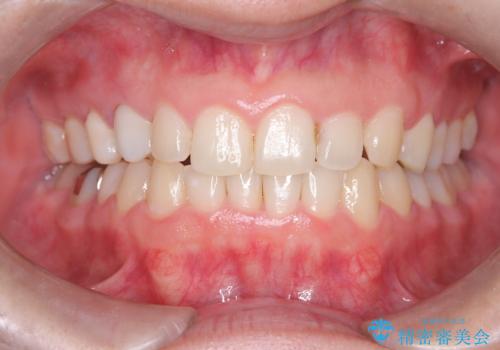

- 下の歯のがたつき(叢生)、真ん中(正中)が右にずれていることを主訴に来院されました。右上前から3番目の永久歯が埋まっている(埋伏)していることから正中は可能な限り合わせることをゴールとしてマウスピースでの矯正治療を選択しました。

今回の矯正治療では、透明なマウスピース型の装置インビザラインを使用しました。がたつきをとるため、安全性が確保できる範囲で歯と歯の間を少し削り必要なスペースを確保しました。